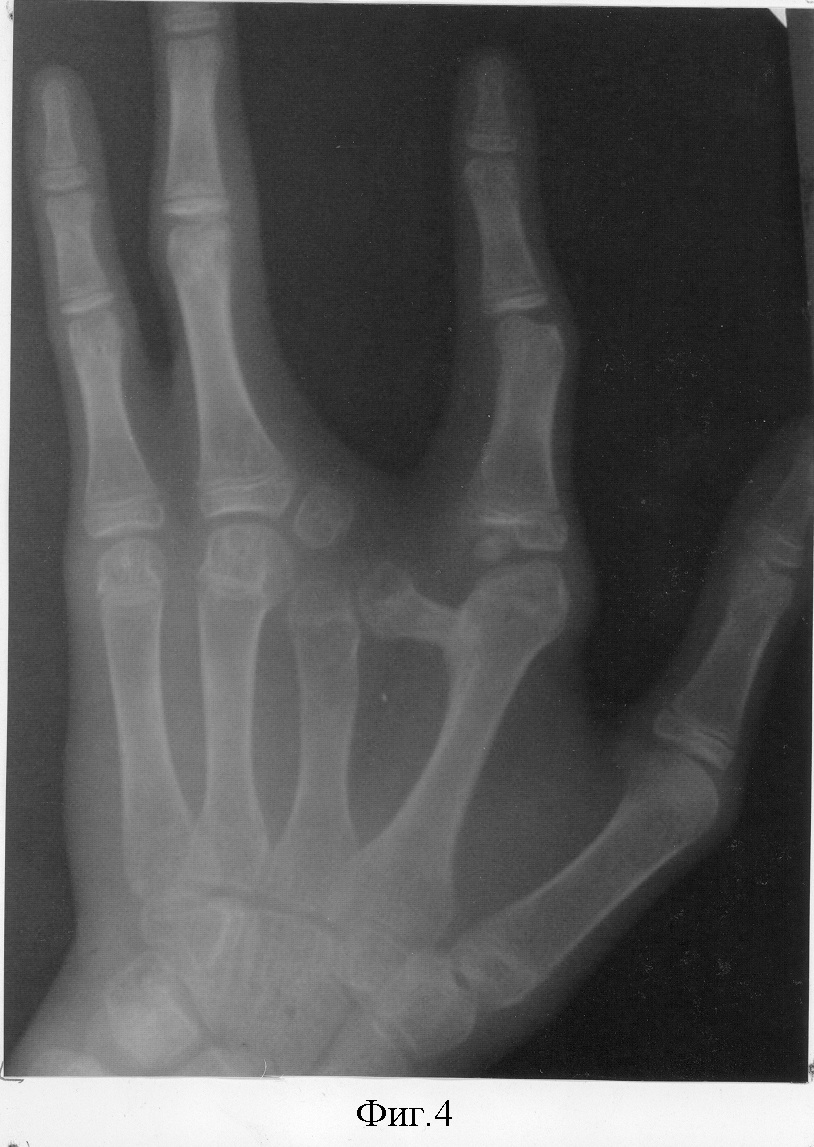

29.05.03 г. в отделении хирургии кисти НИЦТ «ВТО» выполнена операция по вышеописанной методике: ракетообразный разрез по расщелине кисти, с тыльного доступа вычленена головка дополнительной поперечной кости со второго пястно-фалангового сочленения, смещены навстречу друг другу вторая и третья пястные кости до достижения анатомической ширины кисти. Приложив дополнительную поперечную кость с тылу второй пястной кости, определена необходимая длина этой кости, подлежащая удалению. После этого удален лучевой конец дополнительной поперечной кости. Под головкой поперечно перепилена вторая пястная кость, и второй палец вместе с головкой пястной кости ротирован до функциональной позиции второго пальца по отношению к кисти. Достигнутое положение костей фиксировано спицами (фиг.3). Послойные швы на рану. Спиртовая повязка. Гипс до снятия кожных швов. Заживление раны первичным натяжением. Спицы удалены через 2 мес. Контрольный осмотр через 1,5 года. Достигнута хорошая анатомическая структура и улучшилась функция кисти (фиг.4,5).